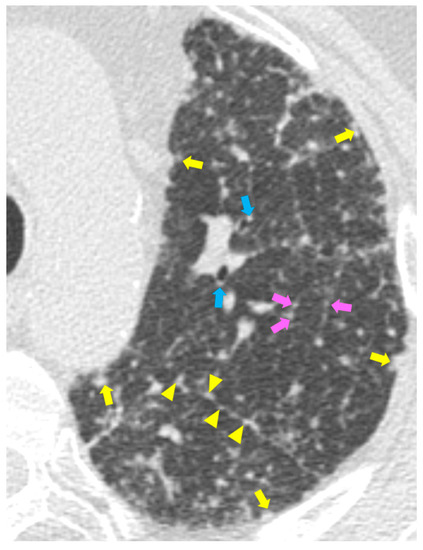

2.2. Typical and Atypical Manifestation of Pulmonary Sarcoidosis at HRCT